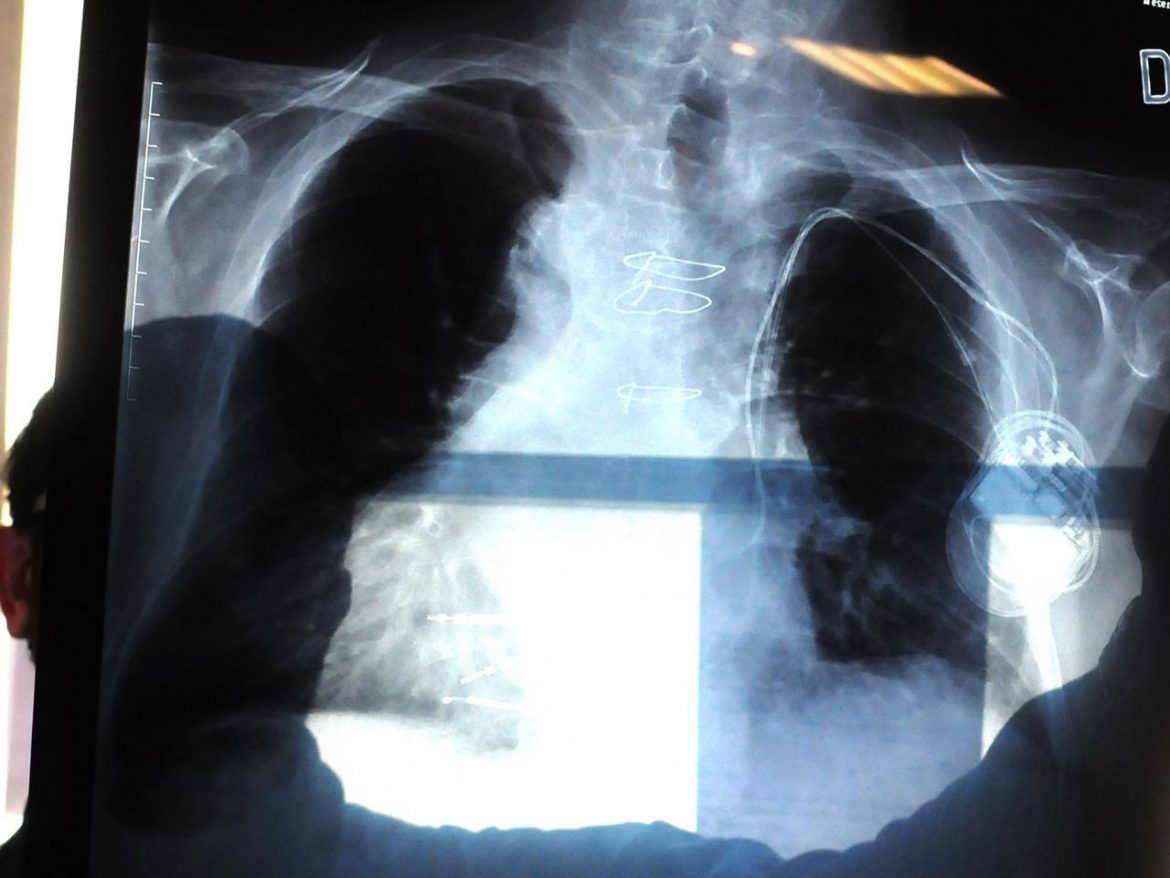

Milano, 21 nov. (Adnkronos Salute) – E’ disponibile da oggi in Italia pralsetinib, nuova terapia target di Roche approvata un anno fa dall’Agenzia europea del farmaco Ema in monoterapia per il trattamento di adulti con tumore del polmone non a piccole cellule (Nsclc) in stadio avanzato positivo per la fusione del gene Ret, non precedentemente trattati con un inibitore di Ret. Il farmaco è ora rimborsato dall’Agenzia italiana del farmaco Aifa per questa popolazione di pazienti in linee successive alla prima.”La ricerca scientifica sta accumulando negli ultimi anni molti risultati significativi nell’ambito del tumore polmonare non a piccole cellule, attraverso l’identificazione di trattamenti sempre più innovativi e mirati verso specifici bersagli molecolari, come nel caso di pralsetinib – commenta Silvia Novello, ordinaria di Oncologia medica all’Università degli Studi di Torino e presidente di Walce Onlus (Women Against Lung Cancer in Europe – Donne contro il tumore del polmone in Europa) – L’approvazione di pralsetinib da parte di Aifa segna un’importante novità per i pazienti con Nsclc positivo a Ret, un’alterazione molecolare riscontrata in circa l’1-2% dei casi di Nsclc”. Si tratta di circa 37.500 persone all’anno nel mondo, spesso più giovani rispetto alla media di chi riceve una diagnosi di cancro polmonare e senza una forte abitudine al fumo, “che possono quindi disporre di un’ulteriore soluzione terapeutica innovativa – sottolinea la specialista – che ha ottenuto ottimi risultati nel controllo della malattia, unitamente a un’efficacia anche a livello delle metastasi cerebrali. E’ un altro tassello nella medicina di precisione applicata al trattamento del tumore polmonare”. Il via libera a pralsetinib si basa sui risultati dello studio di fase 1-2 Arrow, in cui il farmaco ha prodotto una risposta clinica duratura nei pazienti Nsclc con fusioni di Ret. I dati, presentati lo scorso settembre al Congresso della Società europea di oncologica medica Esmo, hanno confermato che anche in presenza di una mediana di follow-up di 26,8 mesi pralsetinib mostra un’attività clinica robusta e duratura, con un tasso di risposta del 63,1% nei pazienti precedentemente trattati con chemioterapia a base di platino e del 77,6% nei pazienti che non avevano ancora ricevuto una terapia sistemica. L’aggiornamento del trial ha inoltre confermato il profilo di sicurezza e la tollerabilità del farmaco. “I pazienti italiani con tumore al polmone in stadio avanzato con alterazione di Ret oggi possono beneficiare di un’importante innovazione terapeutica che ha dimostrato promettenti risultati in termini di efficacia e tollerabilità negli studi clinici registrativi – afferma Filippo de Marinis, direttore della Divisione di Oncologia toracica dell’Istituto europeo di oncologia di Milano e presidente dell’Aiot, Associazione italiana di oncologia toracica – Pralsetinib al momento è riservato a pazienti con Nsclc metastatico Ret-positivo in linee avanzate di trattamento che non hanno ricevuto altri farmaci specifici per Ret e indipendentemente dal regime chemioterapico precedentemente ricevuto, garantendo massima flessibilità di accesso alla terapia”.”In Roche ci impegniamo da lungo tempo nel campo dell’oncologia polmonare al fine di sviluppare approcci terapeutici all’avanguardia attraverso l’adozione di tecniche innovative e personalizzate che possano dare il via a nuovi percorsi di guarigione o migliorare quelli esistenti – dichiara Federico Pantellini, Medical Affairs Lead Roche Italia – Siamo quindi lieti di aver ricevuto l’approvazione di pralsetinib da parte di Aifa”, perché “in questo modo potremo fare un ulteriore e importante passo avanti nella nostra missione di fornire ai pazienti il giusto trattamento nel miglior modo possibile, aiutandoli così ad apportare un effettivo miglioramento nella propria vita”.